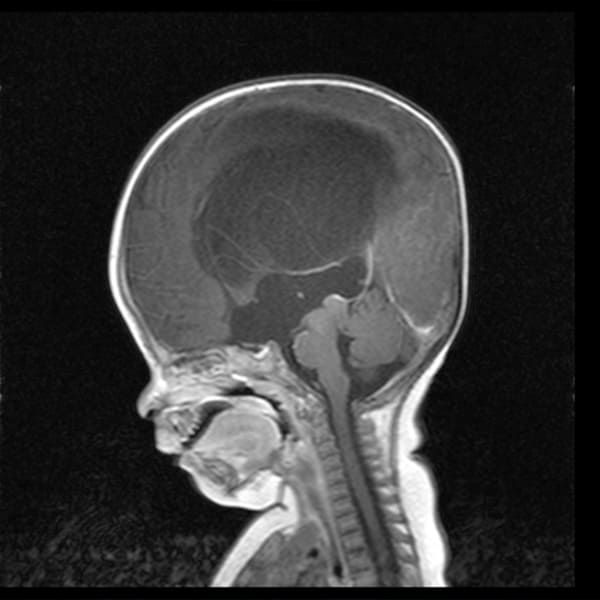

Malformación Chiari

Descompresión de la fosa posterior, se extrae una pequeña sección de hueso de la parte posterior del cráneo, aliviando la presión al darle más espacio al cerebro.

Cirugía craneal

Intervención que trata problemas en el cerebro o las estructuras circundantes. Puede ser necesaria para intervenir un tumor, por sangrado por traumatismos, problemas de los vasos sanguíneos, infecciones en el cerebro, presión craneal, y ciertas enfermedades como la epilepsia o el párkinson.